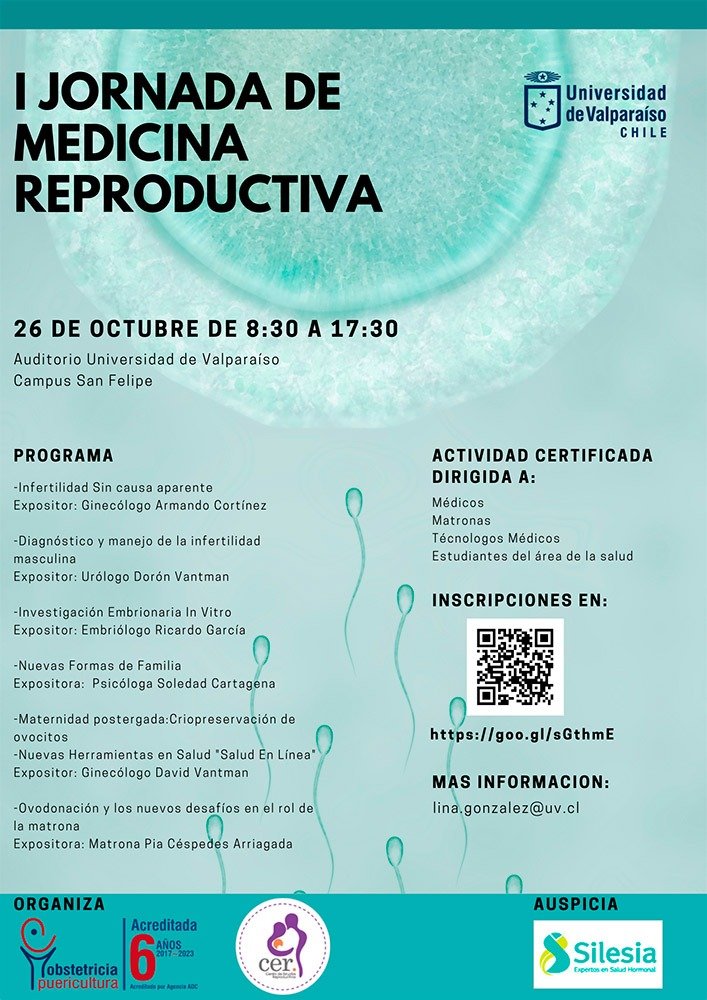

Vasectormía: Control de la paternidad

La planificación familiar es un concepto de pareja que tradicionalmente se ha dirigido hacia la mujer, sin embargo, los hombres también pueden adoptar un rol más protagónico en el control de su paternidad siendo la vasectomía un método más seguro, efectivo y económico comparado con su equivalente en la mujer (la ligadura de trompas femenina).